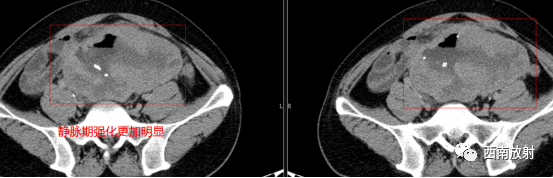

▲病例 间质瘤:男,49 岁,查体发现胃占位性病变 。分别为CT平扫、动脉期及平衡期示胃底处一类圆形软组织结节(箭头),大小约29 mm×28 mm,边界清晰,密度均匀,增强扫描均匀轻度强化[4]。